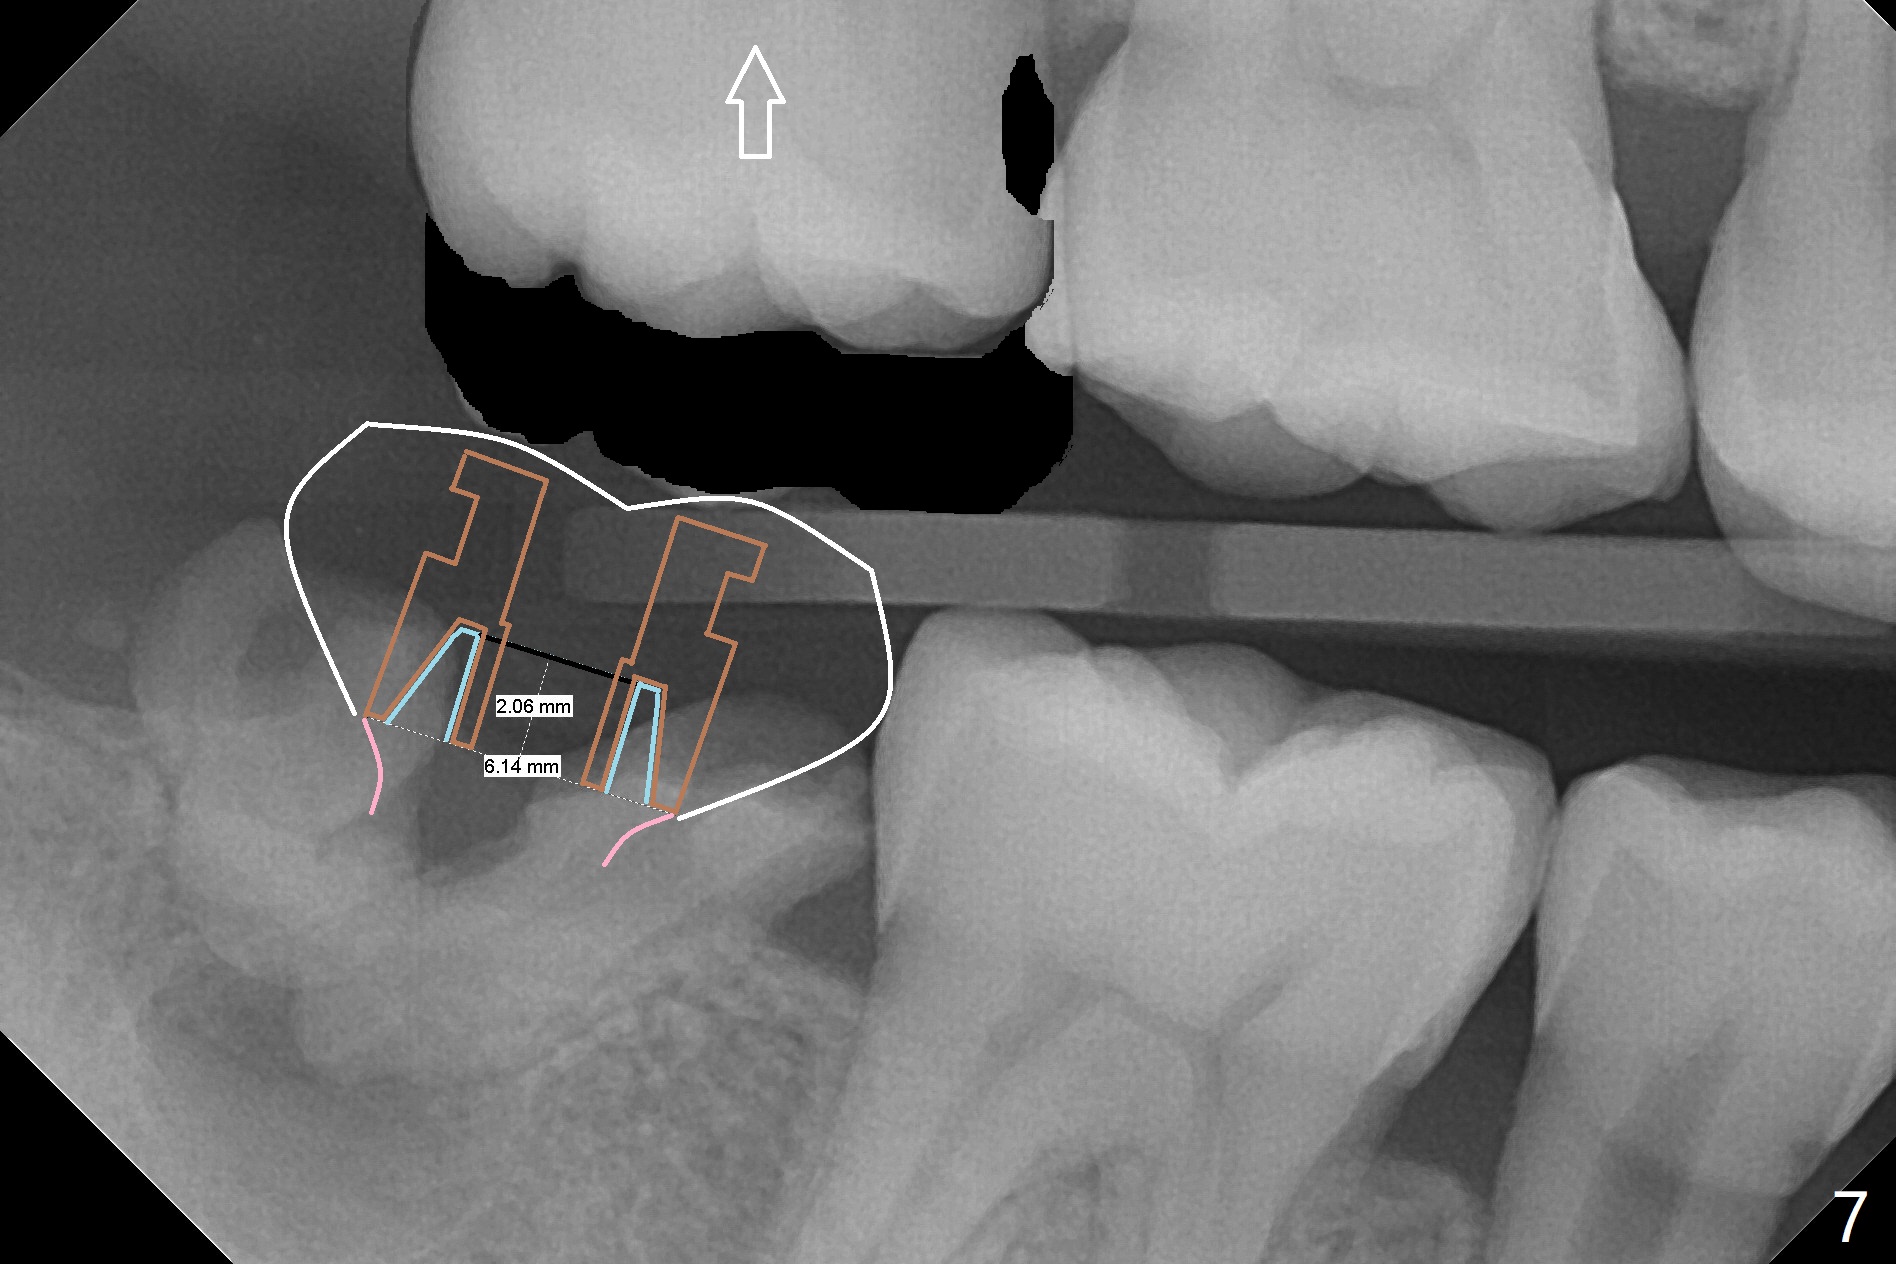

A 39-year-old man finishes orthodontic treatment without intrusion of the upper 2nd molar (Fig.1). He is reluctant for mini-implant placement for intrusion. After extraction of the tooth #31 with periapical radiolucency (Fig.2 *), a 5x11(4) mm Magicore will be placed with guide (Fig.3). Following osteointegration (Fig.4), a burn out core is going to be placed (Fig.5 brown, inside metal, outside plastic). With proper height adjustment, a provisional is fabricated around the core with acrylic (Fig.6 white). If the provisional keeps breaking down under occlusion, the case will be sent to lab for a screw retained crown with unfinished rough occlusal surface so that a thin layer restoration material able to be laid chair-side (acrylic or suction down material). Over time, the opposing tooth will be intruded (Fig.7 arrow).